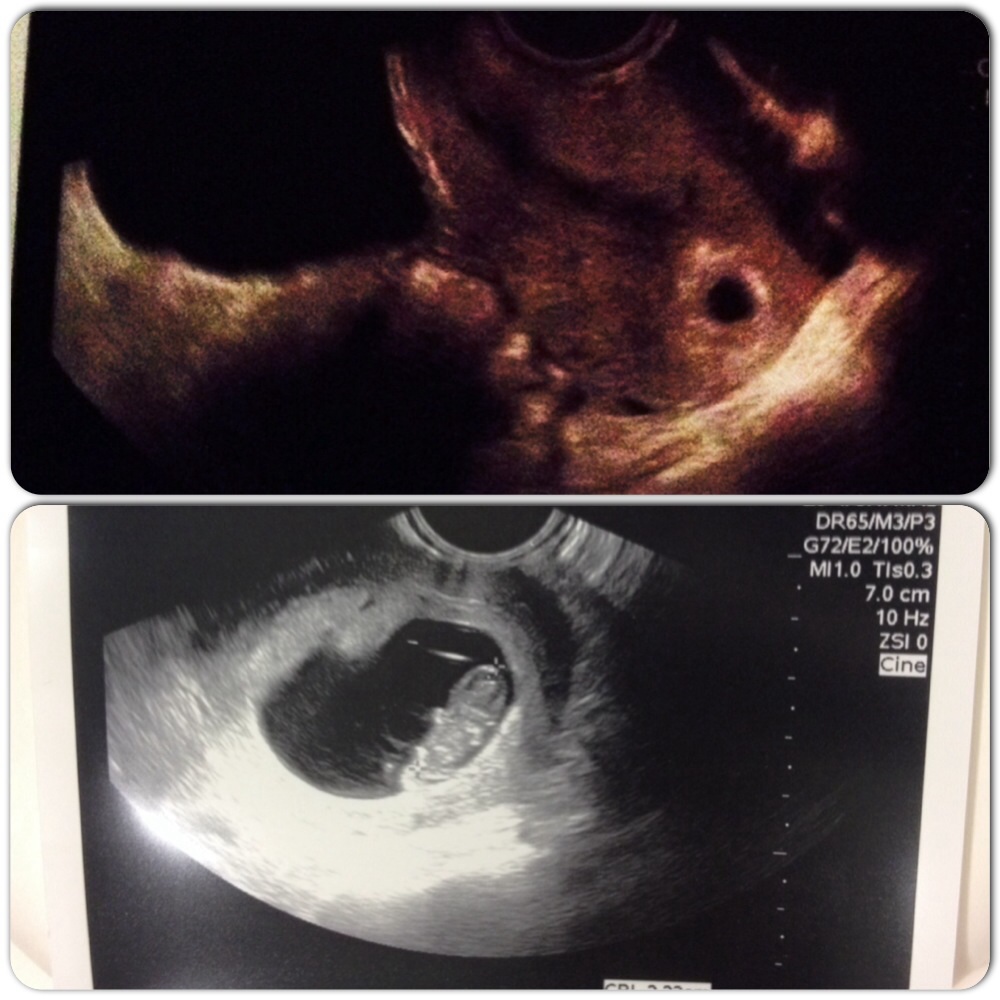

Me 29 DH 30 Unexplained IF TTC since wedding May 2012. IUI #1 11/5/13-BFN. IUI #2 12/5/13-BFN. IUI #3-12/30/14. All three with Femara CD 3-7 and Ovidrel trigger. +HPT 1/13/14 First +ever!!! Beta #1 195 Beta #2 1/15-533. Ultrasound on 2/4 showed one bean. EDD 9/22/14. Team Green turned Team Blue-Baby Conner arrived on 9/19/14.

Thanks everyone!! We even saw the baby's lil arms moving and kinda putting his lil fingers in his mouth to suck it haha amazing feeling! DH was teary-eyed when he saw d flickering heartbeat. :x